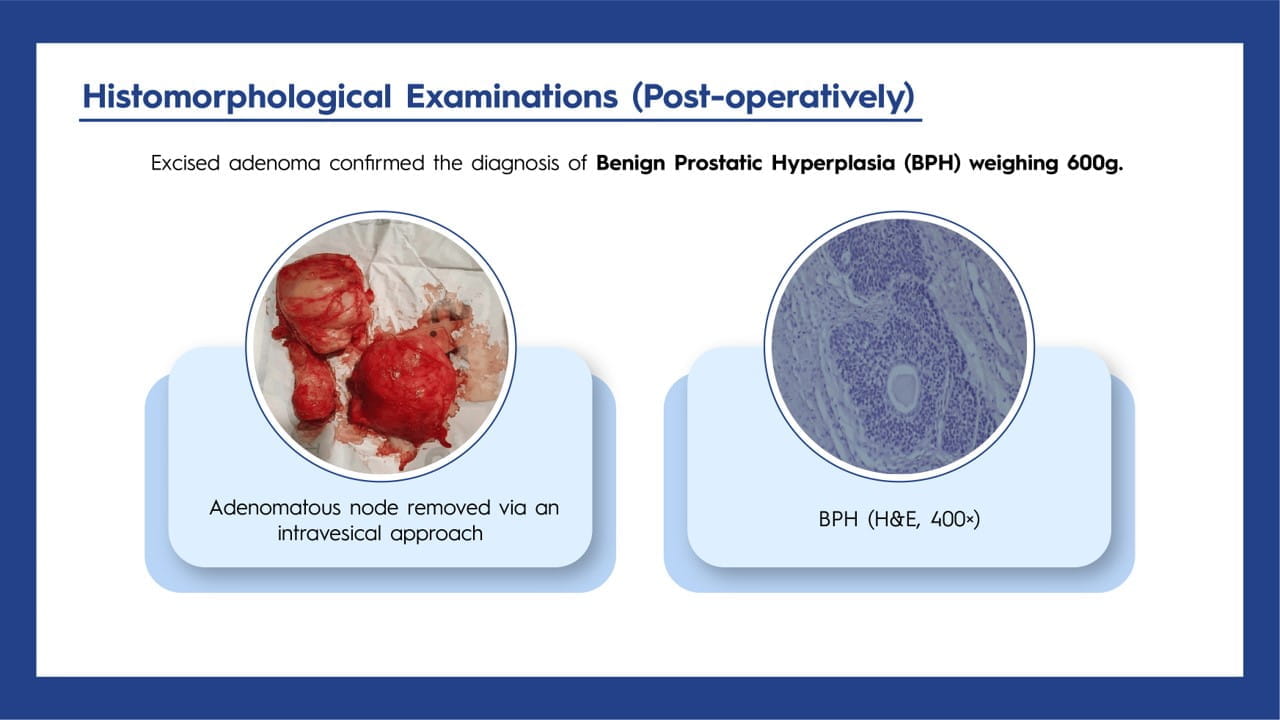

BPH, a common condition in older men, can occasionally progress to giant prostatic hyperplasia, where the prostate gland exceeds 500 g. Surgical options may be considered for complications that are challenging to manage with medication. In this case study, the patient successfully underwent a transvesical prostatectomy to treat a significantly enlarged prostate weighing 600 g.